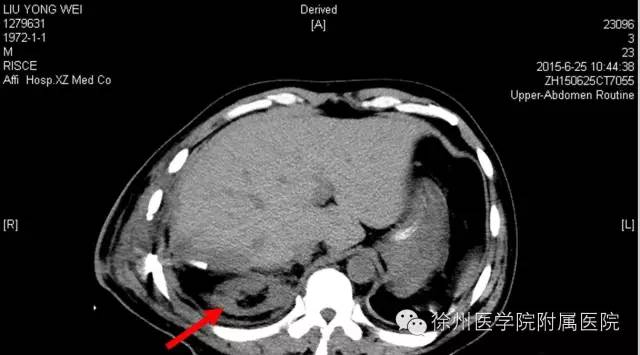

图二 2015年6月25日(术后第5天)CT,右肾如箭头所示。

该声明还专门张贴了两张CT复查图。

图一 2015年6月21日(术后第1天)CT,右肾如箭头所示。